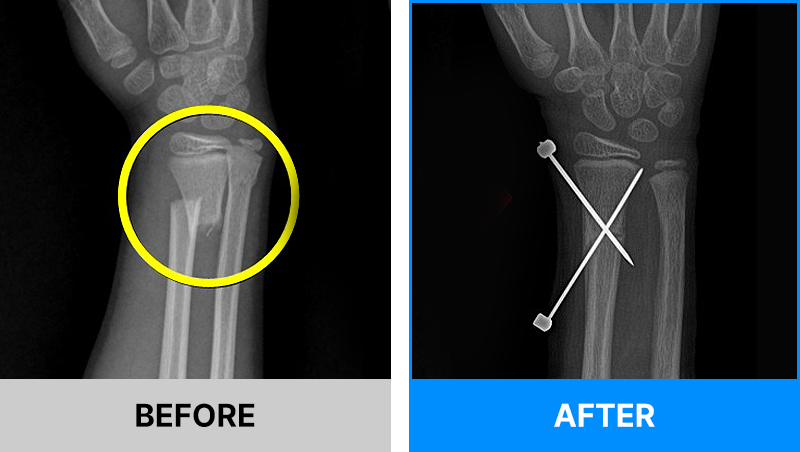

왜 당일 입퇴원 수술일까요?

오래 입원할 필요가 없기 때문입니다.

서울거탑정형외과에서는 전신마취, 척추마취가 아닌

국소부분마취(신경차단) 및 수면 마취를 통해 수술을 시행합니다.